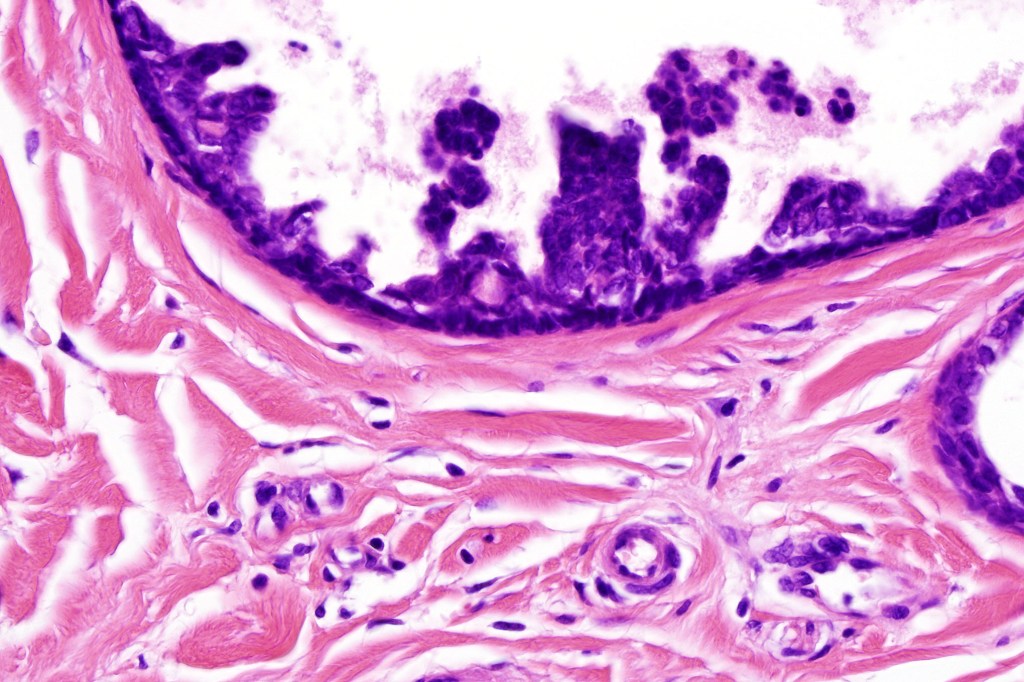

•Ducts lined by double-layered epithelium- small inner, uniform cells with eosinophilic cytoplasm & vesicular/hyperchromatic nuclei with small nucleoli & outer myoepithelial cells

•No pleomorphism and mitoses are sparse of absent

•Pseudo-papillae (devoid of a fibrovascular core) are often conspicuous

Absense of true papillae (i.e with a fibrovascular core)